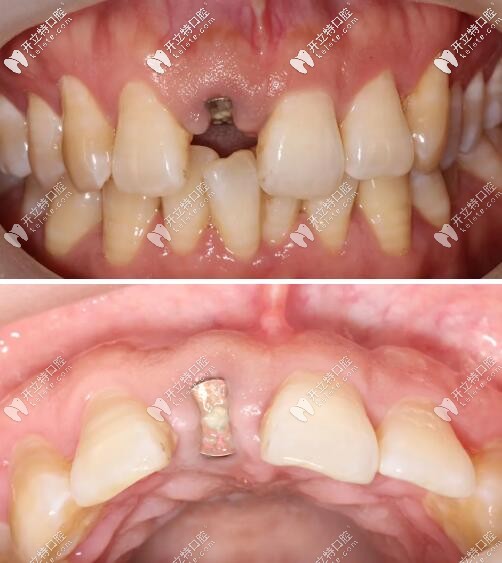

術(shù)后四個(gè)月,制取閉口式印模,制作樹脂臨時(shí)牙冠,口內(nèi)戴入;

X線顯示:臨時(shí)修復(fù)體就位良好;

門牙外傷過渡義齒修復(fù)